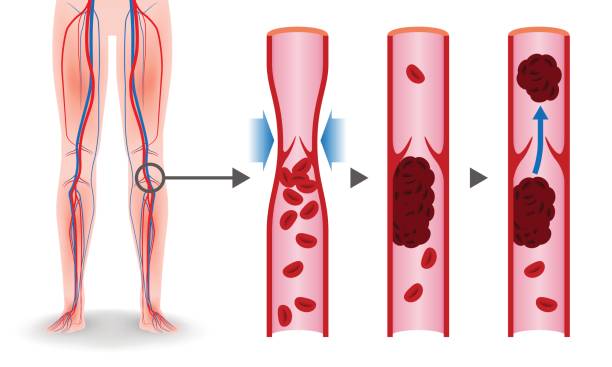

血栓性静脈炎とはの説明スライド - 医療のイラスト・写真・動画、素材販売サイトのメディック medick。

人間の血管の医療静脈血栓の図イラスト画像とPSDフリー素材透過の無料ダウンロード - Pngtree。

脚領域における深部静脈血栓症の医学的図。のイラスト素材・ベクター Image 98030310。

正常な血管と血栓ができた血管 イラスト素材5358451- フォトライブラリ。

血栓ができている血管 イラスト素材6665451- フォトライブラリ。